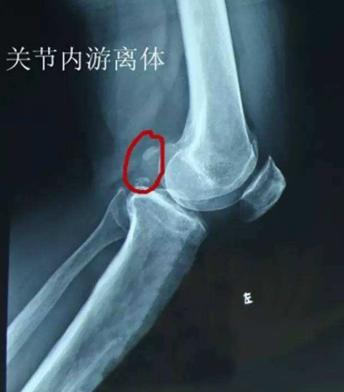

关节软骨无法在特定位置转变为骨骼,直接令到这区域的软骨增厚,增厚的软骨与周围正常的软骨分离形成了皮瓣,这一系列过程便称之为OCD。异常软骨的皮瓣有可能会发生从关节表面脱离,形成“关节鼠”。

图为“关节鼠”

那么,什么是“关节鼠”?

这一术语较好理解,意指关节出现病变的时候,在关节软骨内部会有自行脱离的“小碎片”。如前文提到,关节之间有“小碎片”的存在,容易发生疼痛等一系列影响。